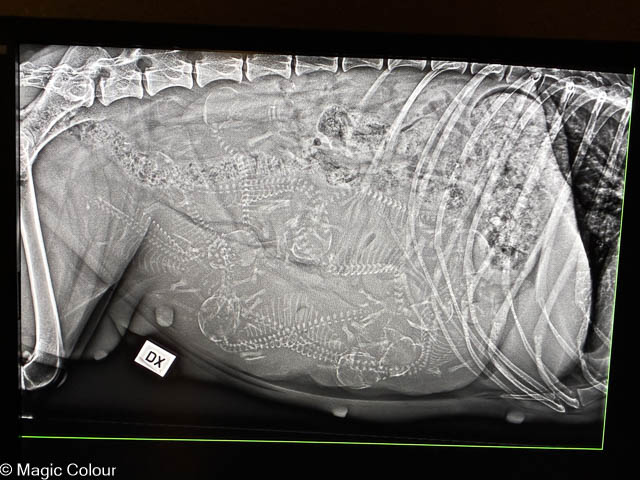

2025-11-13 Bella på dräktighets röntgen

Idag har vi varit och tagen dräktighet röntgen på Bella. Och det finns helt säkert 8 enligt veterinären och det kan finnas 9 valpar i magen. Vi tycker vi kan räkna 9 skallar och ryggrader och räknar vi på vikten som Bella har gått upp stämmer det med 9 valpar. Så nu får vi vänta till nästa helg för att se vem som har rätt – veterinären eller vi.